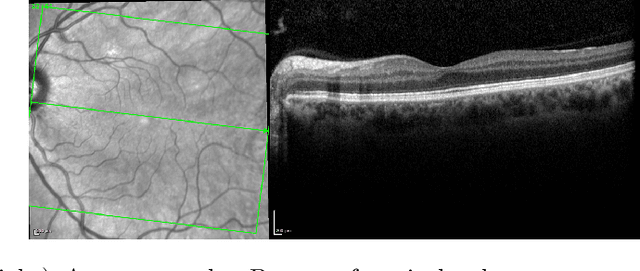

Abstract:The estimation of glaucoma progression is a challenging task as the rate of disease progression varies among individuals in addition to other factors such as measurement variability and the lack of standardization in defining progression. Structural tests, such as thickness measurements of the retinal nerve fiber layer or the macula with optical coherence tomography (OCT), are able to detect anatomical changes in glaucomatous eyes. Such changes may be observed before any functional damage. In this work, we built a generative deep learning model using the conditional GAN architecture to predict glaucoma progression over time. The patient's OCT scan is predicted from three or two prior measurements. The predicted images demonstrate high similarity with the ground truth images. In addition, our results suggest that OCT scans obtained from only two prior visits may actually be sufficient to predict the next OCT scan of the patient after six months.